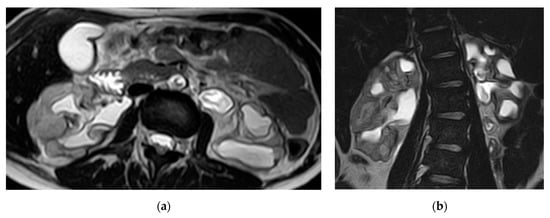

2.2. Renal and Perinephric Abscesses

| Renal abscesses | Round or geographic non-enhancing central fluid collection and enhancing rim. Perinephric fat stranding and thickening of Gerota’s fascia. |